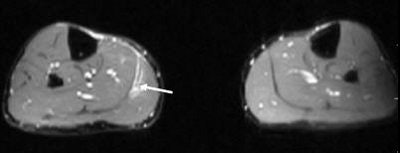

![]() |

| Coronal T2-weighted MR image of the legs shows the fluid in the myofascial junction (black arrowhead) as well as slight proximal retraction of the medial head of the gastrocnemius muscle from its musculotendinous junction (white bracket). Images courtesy of Dr. Douglas Beall. |